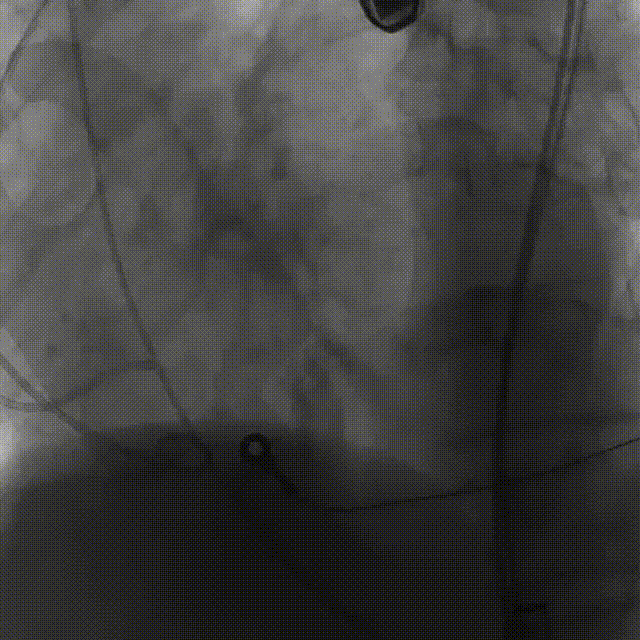

5.根据术前评估及球囊预扩情况,选择23mm沛嘉TaurusElite瓣膜进行植入,抓捕器辅助下输送器头端进入左室,零位定位

6.在150次/分快速起搏下释放瓣膜至工作位

7.瓣膜释放至工作位后造影示左右冠灌注尚可,瓣膜形态尚可,决定予以释放

8.造影见明显反流影,瓣膜受限明显,决定予以球囊后扩

9.150次/分快速起搏下以23mm 巴尔特球囊进行后扩张

10.猪尾导管测压显示,平均跨瓣压差约12mmHg,造影示瓣膜定位尚可、开放良好,少量瓣周漏,患者血流动力学指标稳定,血压约100/70mmHg,升主动脉未见造影剂潴留或渗漏,标志手术成功。